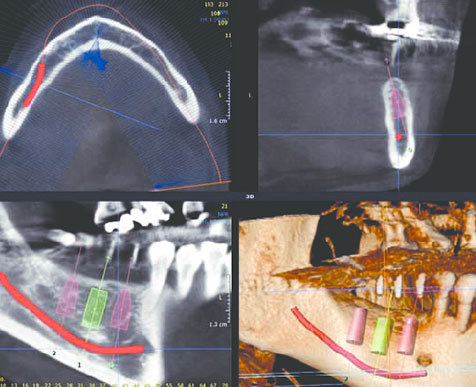

Automatic AI implant planning

Results viewed in interactive 3D